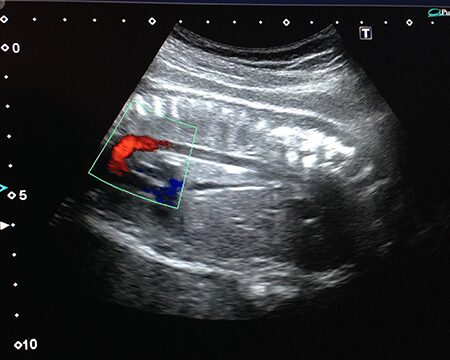

Otro factor a tener en cuenta es la presencia de otras marcadores ecográficos en el feto. En algunos casos, la translucencia nucal puede estar dentro del rango normal, pero si hay otros indicadores en la ecografía, como una malformación cardíaca o un crecimiento anormal del feto, el riesgo de alteraciones genéticas también puede ser mayor.